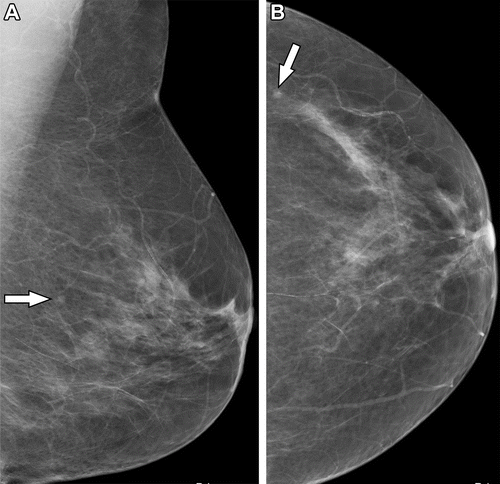

A closer look at the literature suggests the combination of digital breast tomosynthesis (DBT) and two-dimensional (2D) digital mammography (DM) has relatively equivalent cancer detection rates as using DM alone, according to a recent presentation at the Society of Breast Imaging (SBI)/American College of Radiology (ACR) conference.